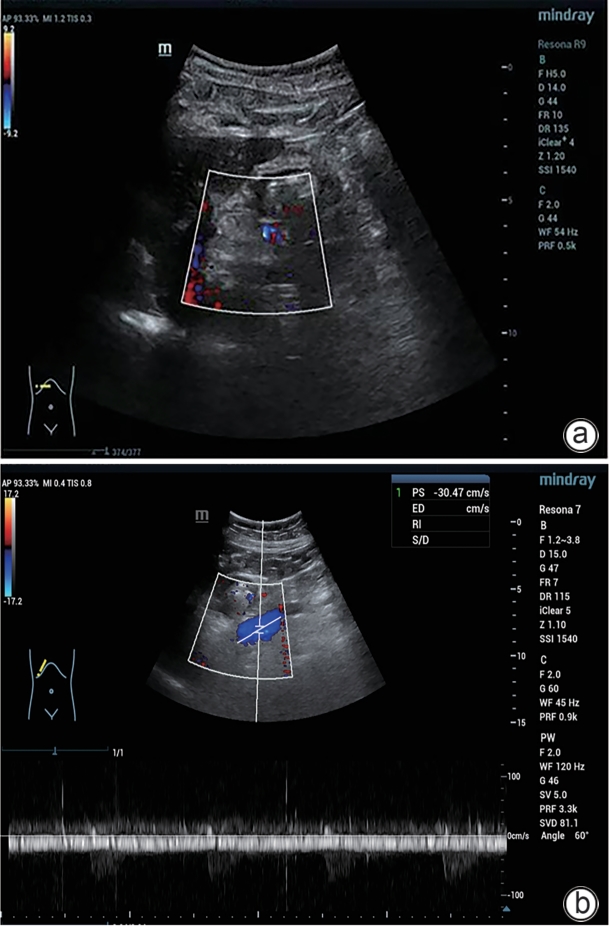

Large spontaneous splenorenal shunt embolization combined with anticoagulant therapy in treatment of portal vein thrombosis: A case report

Ju HUANG, Xiaoze WANG, Xuefeng LUO, Li YANG

2025, 41(8): 1639-1642. DOI: 10.12449/JCH250825

Abstract(513) HTML (178) PDF (3328KB)(71)

Abstract:

Portal vein thrombosis (PVT) is a common and severe complication in patients with liver cirrhosis, and alterations in portal hemodynamics are closely associated with the development of PVT. The presence of large spontaneous splenorenal shunt (SSRS) may lead to reductions in portal vein perfusion and blood flow velocity, which may compromise the anticoagulant effect on PVT. This article reports the treatment strategies of SSRS embolization combined with anticoagulant therapy that help to achieve complete recanalization of the portal vein; however, high-quality clinical studies are still needed to further validate and support the effectiveness of this strategy.